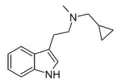

| McPT | artificial | H | CH3 | C3H5 | N-Methyl-N-cyclopropyltryptamine | 1373918-63-8 |

| EcPT | artificial | H | CH2CH3 | C3H5 | N-ethyl-N-cyclopropyltryptamine | |

| PcPT | artificial | H | CH2CH2CH3 | C3H5 | N-propyl-N-cyclopropyltryptamine | |

| iPcPT | artificial | H | CH(CH3)2 | C3H5 | N-isopropyl-N-cyclopropyltryptamine | |